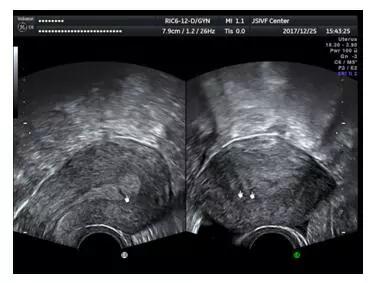

普通二维超声显示的宫腔形态异常

4.三维超声检查,三维超声检查也是经阴道超声,一般是在常规阴道超声检查的基础上加做,通俗的理解,就是立体超声。相比常规阴超,三维超声可以全方位,多切面,多角度来观察子宫内膜及宫腔的环境,可以提供更多的诊断信息。其中最有价值的切面就是冠状切面,即与腹部平行的切面。

由于子宫大部分位置为前位或者后位,所以常规阴道超声很难显示冠状切面。然而三维超声能够直观,整体的从宫体至宫颈将整个子宫长轴冠状面显示出来。阴道三维超声不受方向限制,能够从多个方位对内膜变病进行观察,从每个切面呈像,可以准确,迅速的获得丰富立体的子宫内膜完整图像信息。

适时三维图像还具有自由旋转功能,可以对粘连的部位进一步明确及测量病变面积。在冠状切面,可以显示宫腔及内膜的整体形态,正常情况下是倒三角形,左右对称,双侧宫角锐利,内膜及肌层分界清晰规整,内膜回声均匀。当发生宫腔粘连时,中央性粘连表现为内膜的缺损,回声不均匀等,周围性粘连则可能变现为倒三角形结构的破坏,宫底部或双侧壁的不对称,宫角圆顿,宫腔缩窄,内膜及基层分界不清晰,不规整等。